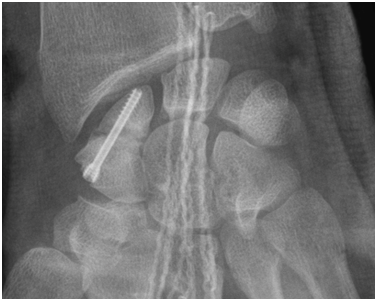

Figure 10 Post-operative X-rays.

The arthroscopic procedure started with the realization of standard radio-carpic initial portals; medium-carpal portals helped with the identification of the pseudarthrosis focus (Figure 4). The pseudarthrosis focus was blown out (Figures 5 & 6). The spongious graft of the contralateral iliac crest was harvested. Placement of the graft through the midcarpal portal of visualization by adapting the arthroscopy trocar (Figures 7-9). The traction was withdrawn. The graft was fixated with a percutaneous anterior approach and arthroscopic support and placement of the double compression screw with radiographic support (Figure 10).